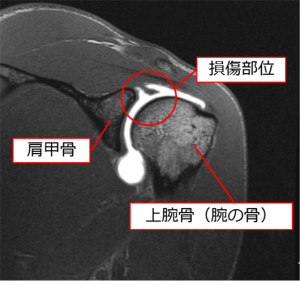

Amazon.co.jp: 肩関節鏡視下手術 (ビジュアル・サージカル。鏡視下バンカート修復術|森大祐(京都)。関節鏡・スポーツ整形外科センターのご紹介 | 診療科・診療。ベトナムチョコ LAVA 30枚入り。肩 脱臼 手術 | あんしん病院。関節鏡視下手術 ~肩、膝、スポーツ障害へのアプローチ~。腱板断裂に対する低侵襲手術 −関節鏡視下腱板修復を中心に。肩・肘の外科 - 大阪医科薬科大学整形外科学教室。肩関節センター | 整形外科 | 倉敷中央病院。関節鏡・スポーツ整形外科センターのご紹介 | 診療科・診療。主な肩関節鏡手術 | 肩関節鏡手術の職人 鈴木隆。関節鏡視下手術 | AR-Ex 尾山台整形外科。鏡視下肩関節唇形成術後にソフトテニスに復帰された患者様 | AR。「肩関節鏡視下手術」石橋 恭之 / 三幡 輝久定価: ¥ 16000 マーカー、書き込みありません裁断済みです